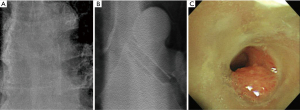

Of the total 213 cases, 121 (121/213, 56.8%) cases of stent obstruction were caused by granulation tissue or fibrosis. The ability of DTS to detect granulation tissue or fibrosis at the end of the stent was significantly better than that of CXR (Figure 1B). The sensitivity of DTS was 64.5% (95% CI, 55.3–73.0%), specificity was 85.9% (95% CI, 77.1–92.3%), and accuracy was 73.7% (95% CI, 67.3–79.5%). For CXR, the sensitivity was 19.0% (95% CI, 12.5–27.1%), specificity was 100.0% (95% CI, 96.1–100.0%), and accuracy was 54.0% (95% CI, 47.1–60.8%) (Table 3). As shown in Figure 2, granulation tissue grew on the distal end of the LMB stent and caused a partial obstruction. As shown in Figure 3, fibrosis occurred at the end of the mid-tracheal stent, creating an airway obstruction.